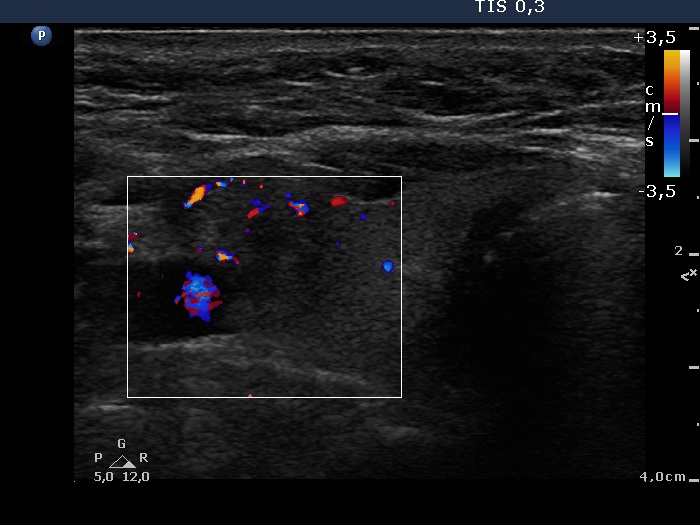

4 years after initial investigation (ultrasonographic picture 3)

Right lobe, horizontal view

Right lobe, horizontal scan, color Doppler mode. The lesion presents signs of perilesional vascularity.